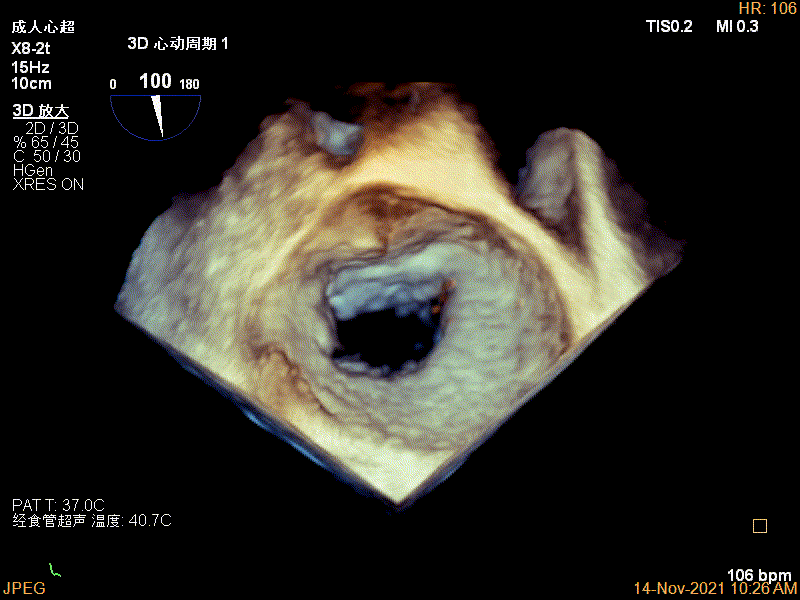

Qlab软件勾画估测瓣口面积约:6.52cm²

3D视图下进夹子并建立trajectory

3D视图打开夹子

3D视图下进第二个夹子并建立trajectory

3D视图两个夹子近似并排排列